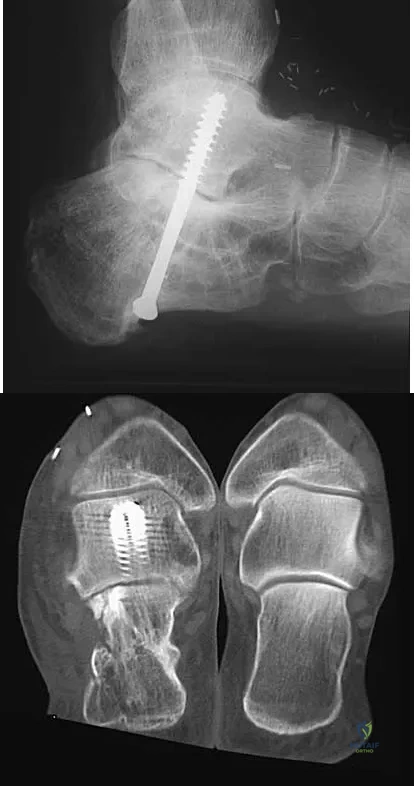

Question 94

A 45-year-old man has persistent hindfoot pain that is aggravated by weight-bearing activities. History reveals that he sustained a calcaneus fracture 2 years ago, and he underwent a subtalar fusion 1 year ago. Examination reveals tenderness in the sinus tarsi and across the transverse tarsal joint. A plain radiograph and a CT scan are shown in Figures 24a and 24b. A technetium Tc 99m bone scan reveals uptake at the subtalar joint and at the transverse tarsal joints. Management should now consist of

Explanation